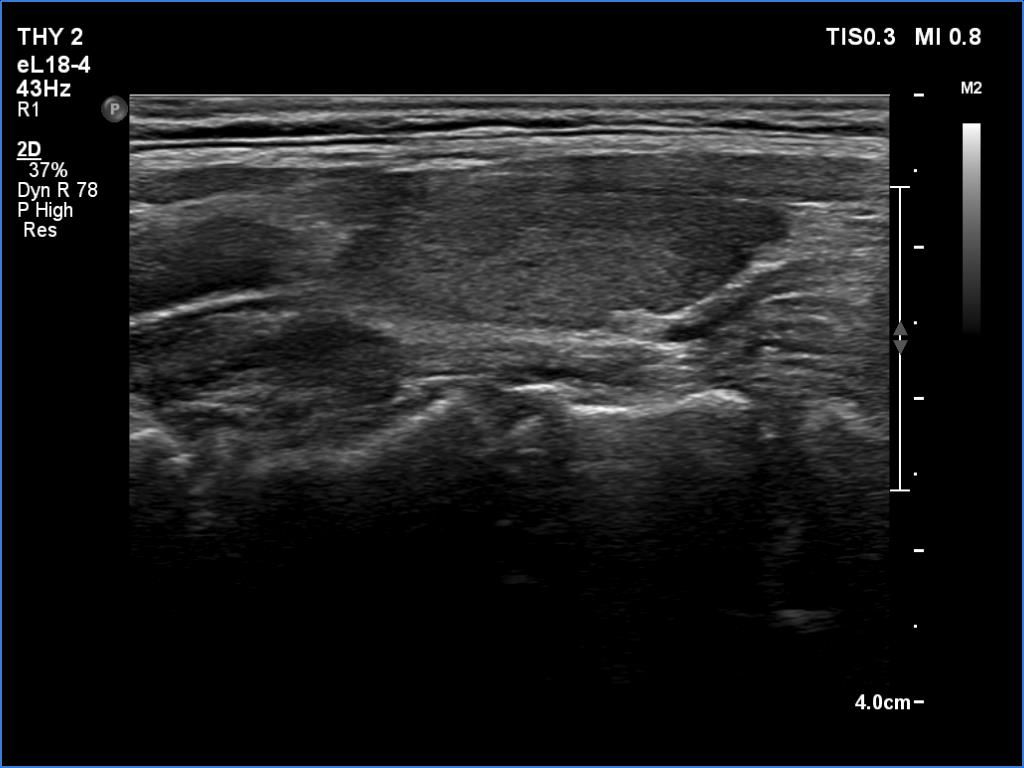

Examination a year after the first visit (ultrasonographic picture 6)

Left lobe, longitudinal scan.